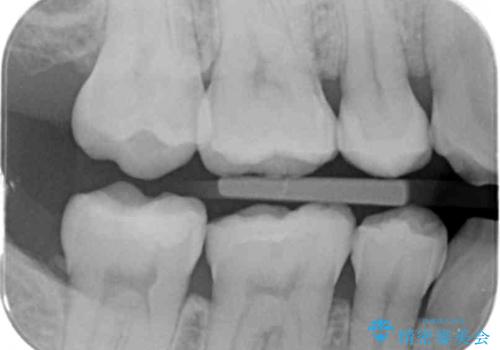

レントゲン画像からは読み取りづらいですが、視診にて歯の一部が黒く透けているのが確認できました。

小さな虫歯でも見落とさずに精度の良い修復をすることで二次う蝕のリスクを減らすことができます。